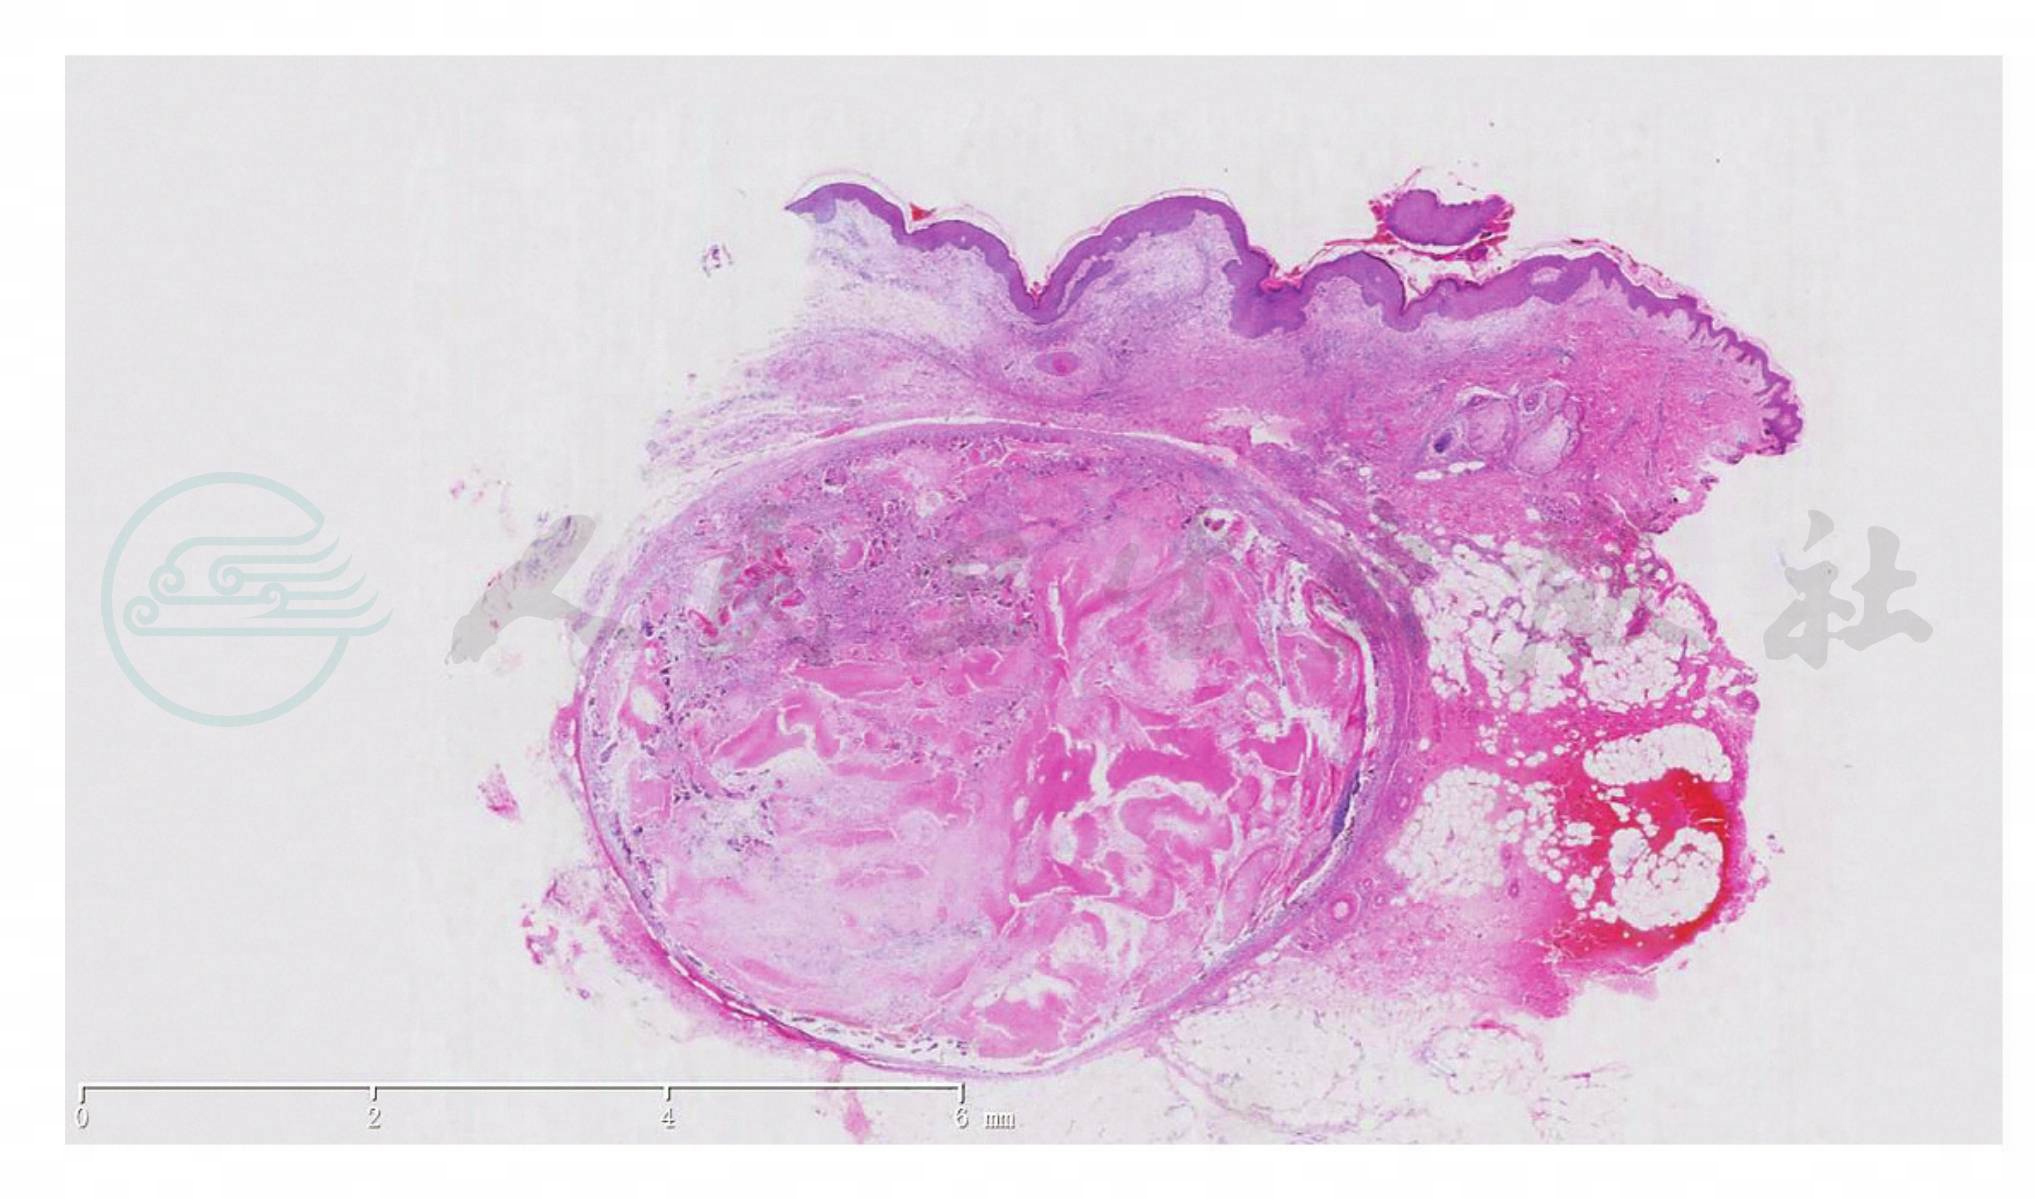

该瘤是向毛母质方向分化的肿瘤。表皮一般正常,但有时可见经表皮排出现象、皮肤松弛及水疱形成。肿瘤位于真皮内,有时可到皮下脂肪。瘤细胞常聚集成多叶状,有时可被邻近被挤压的结缔组织形成的纤维假包膜包绕。单个肿瘤小叶团块由基底样细胞和影细胞混杂构成,皮损处于发展阶段时以前者为主,成熟的皮损以后者为主。基底样细胞体积小、大小形态一致,核圆、呈空泡状,核仁明显(图1~图3)。

图1毛母质瘤。肿瘤由嗜碱性细胞团及影细胞构成(HE染色,×40)

图2毛母质瘤。真皮中下层界限清楚的结节,内含少量嗜碱性小细胞团及大量影细胞(HE染色,×40)